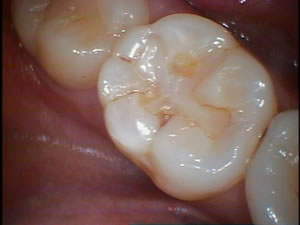

左は新たな奥歯の溝の虫歯です。

右は昔にレジン(樹脂)充填された歯ですがそのまわりが黒く虫歯になってきています。

レジン充填は何年も経過すると接着不良や破折で縁が黒くなったり、虫歯になってくる事もあります。

左の健康で削られていなかった歯の溝ですら虫歯になるのですから、人工的な接着剤でつけられた修復物も再度虫歯になってもしょうがない事かもしれません。